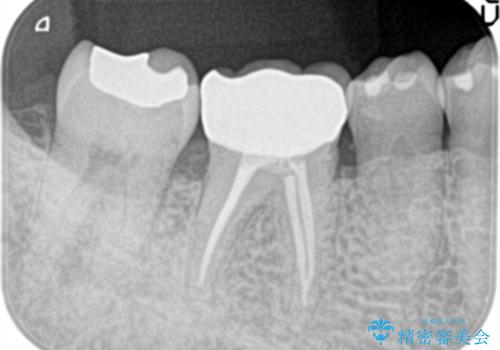

- 定期検診にて膿の出口を見つけたことを主訴に来院されました。

検査の結果、診断を歯髄壊死、症候性根尖性歯周炎とし抜髄を行っております。

- 精密根管治療(イニシャルケース,大臼歯):122,000円、ファイバーコア:22,000円費用は治療当時の料金となります

根管充填はCWCTにて行なっています。